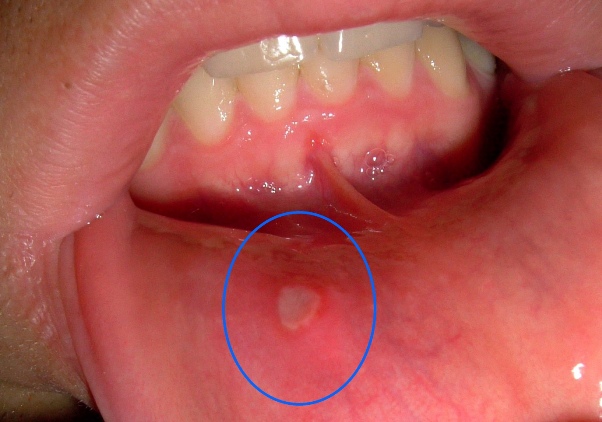

Afte su mali, ali izuzetno neugodni i bolni problemi koji se javljaju u usnoj šupljini. Mnogi su se suočili s ovim neugodnostima, koje često otežavaju osnovne svakodnevne aktivnosti kao što su jelo i govor. Ove ranice, koje mogu biti različitih veličina i oblika, mogu se javiti iznenada, a razlozi za njihovo nastajanje su raznoliki, uključujući stres, hormonalne promjene ili čak alergijske reakcije. Ponekad je izazovno pronaći rješenja koja će pružiti olakšanje i ubrzati proces ozdravljenja. U ovom članku istražit ćemo prirodne metode koje mogu pomoći u ublažavanju simptoma i ubrzavanju procesa ozdravljenja.

Dok su afte obično benigni problemi koji prolaze same od sebe, postoje situacije kada je neophodno potražiti stručnu pomoć. Ako se afte često ponavljaju, traju duže od dvije sedmice, ili su ekstremno bolne, važno je konsultovati se s ljekarom. Također, obratite se stručnjaku ako su afte praćene visokom temperaturom, otečenim limfnim čvorovima ili osipom na tijelu. Ovi simptomi mogu ukazivati na ozbiljnije zdravstvene probleme koji zahtijevaju medicinsku intervenciju.